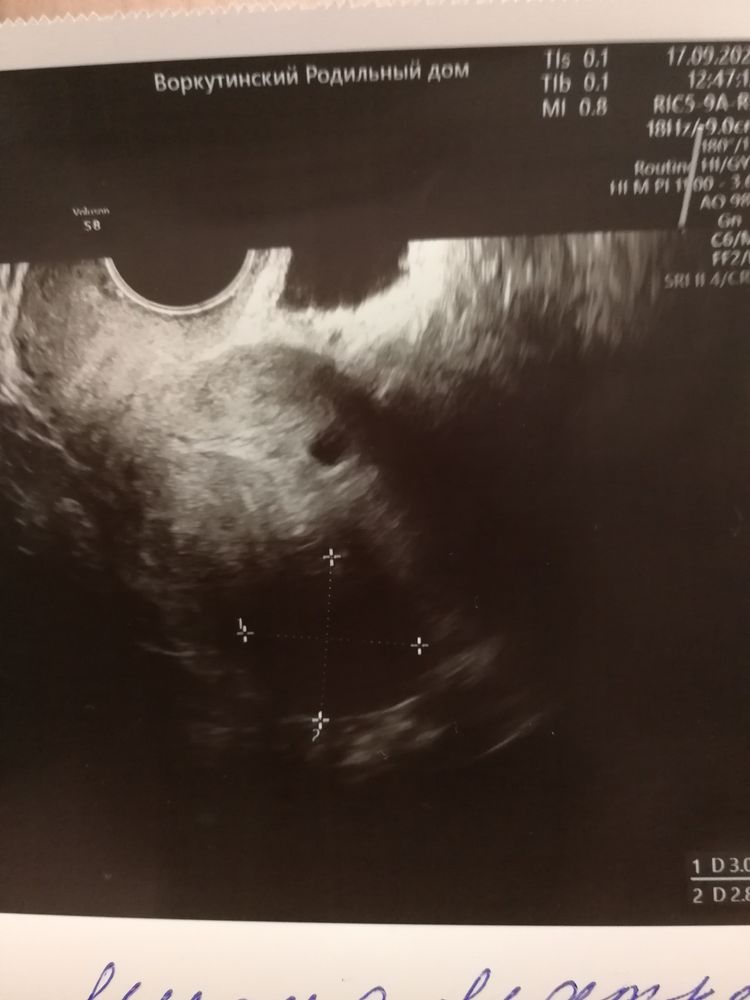

Узи на 13 день цикла Узи на 23д.ц